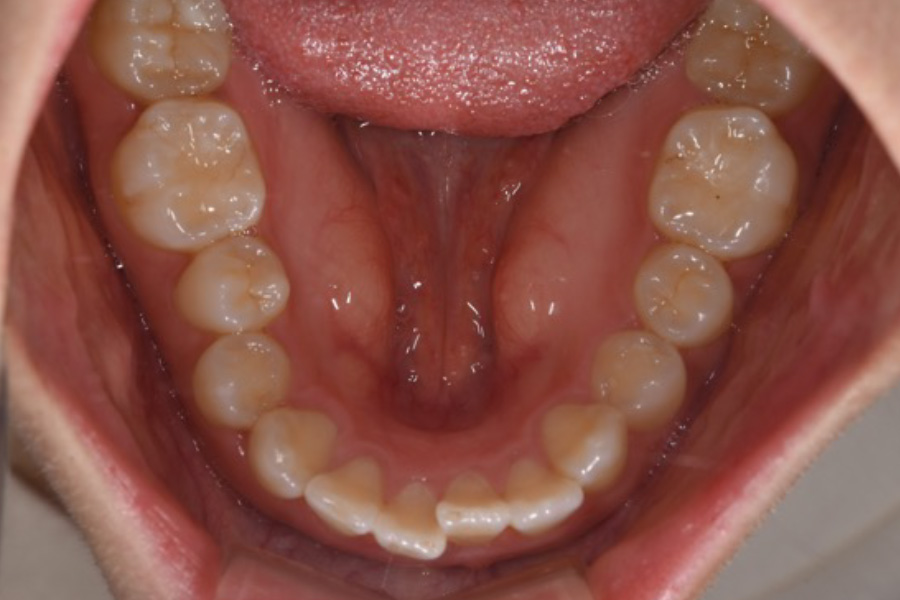

治療前

治療後

主訴 歯並びを治したい

期間 5か月

費用 マウスピース矯正(キャンペーン)

434,000円(税込)

治療内容 目立ちにくいマウスピース矯正(非抜歯矯正)

歯と歯の間に隙間をつくることにより、歯列弓を広げながら治療を行いました。

治療に伴うリスク ・後戻りする可能性があるのでリテーナーを最低でも矯正期間以上はつけること

・稀にほっぺた、唇、舌などに口内炎や傷ができることがあります